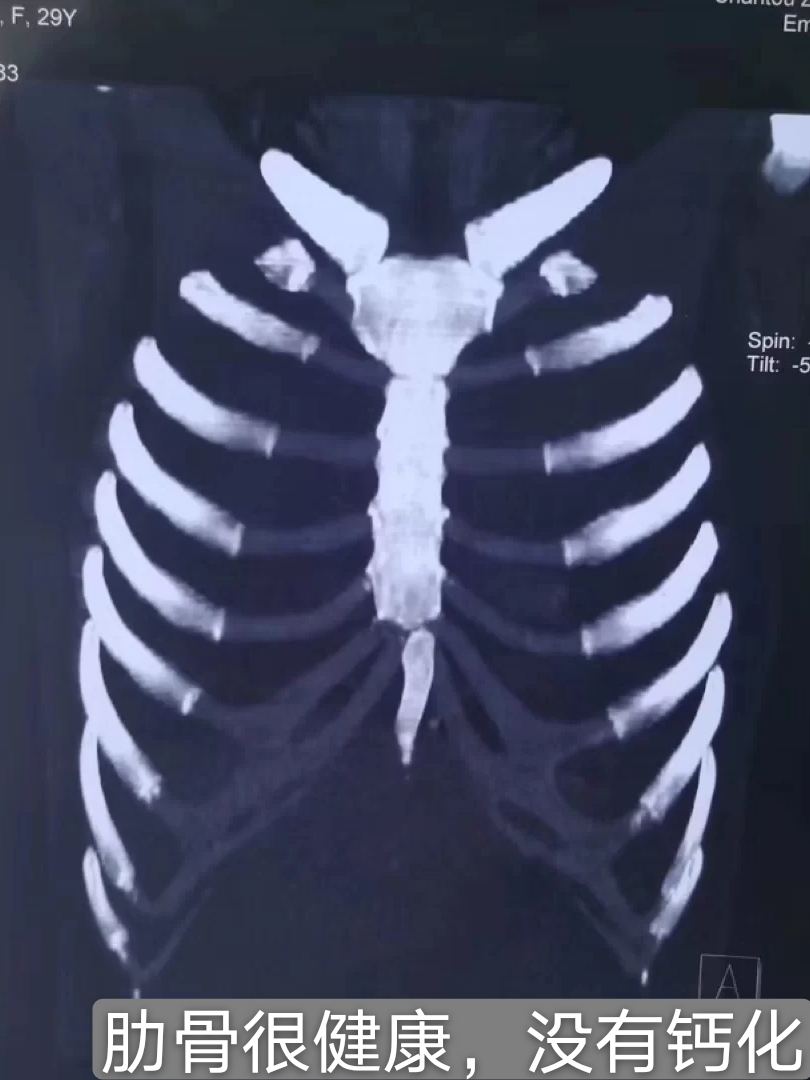

不一定啦,要看钙化的程度。

✔️:轻微的钙化,一样可以用来做鼻综合的支架,一般胸片图的肋软骨位置,显示的是点状白色,那移植的软骨基本不会再钙化。

✔️:轻微钙化虽然也可以用来做支架,但是这对医生的雕刻、技术,太考验了。因为钙化是会导致假体变硬,是不利于雕刻的。稍有偏差就雕刻不好,这超级考验医生的技术和耐心了。